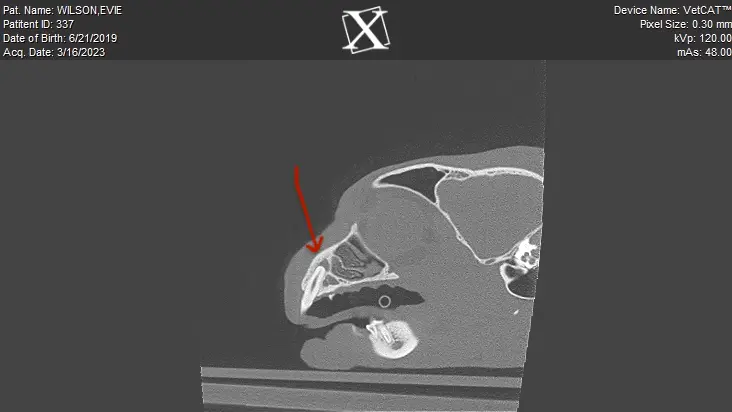

Utilization of CBCT is not relegated to dogs only. We use our CBCT on all cats as well, as we can identify a lot of pathology that is more subtle on conventional dental films. Below is a right maxillary canine tooth of a cool cat named Evie. She had a fractured canine tooth that the owner and family veterinarian noted. Our plan was to either perform a root canal or surgical extraction of the tooth. (When a tooth is broken and the pulp is exposed, there are two treatment plans…root canal therapy or surgical extraction. Watching it closely is not an option!)

We performed CBCT and the images were startling. There was a significant lesion at the apex of the tooth indicating either an abscess or granuloma, and the root end was resorbing. This tooth was therefore surgically extracted. The dental image of the same area did show a wide pulp cavity compared to the opposite canine tooth, but one could not truly appreciate the extent of the root end disease that was evident on CBCT.